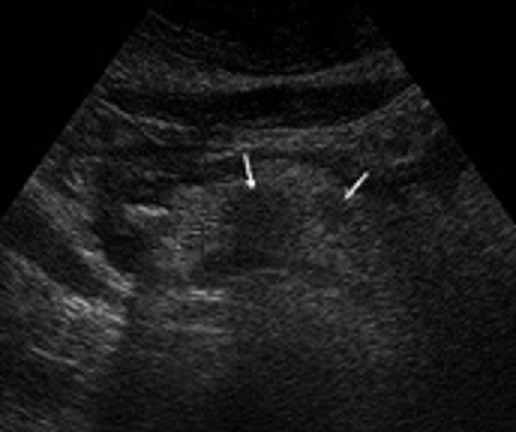

Image echographique d'un

pancreatite aigue form necrotique hemorragique .

Pancreas est volumineuse ,a bord irregule ,

parenchyme oedemateuse hyp[oechogene non homogene en

accosiation des zone necrotique hypoechogene (

fleche blanche ) . Epanchement peripancreatique est

tres marquee |